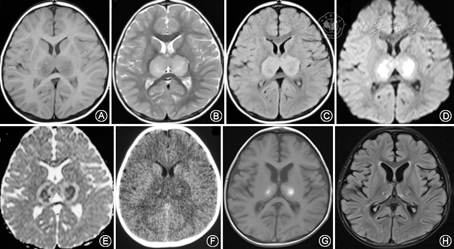

血常规检查:白细胞正常,中性粒细胞占比0.82,C反应蛋白54.6 mg/l,降钙素原115.21 ng/ml;血生化:谷丙转氨酶 210 U/L,谷草转氨酶 388 U/L,乳酸脱氢酶870 U/L,肾功能、电解质、血糖、血氨、血乳酸、丙酮酸均正常。凝血功能、铜蓝蛋白、同型半胱氨酸正常,呼吸道病原IgM抗体8项(包括甲型、乙型流感病毒)均阴性,血、尿有机酸遗传代谢筛查(-)。视频脑电图:背景活动慢、弥散性慢波。病程3 d脑脊液:白细胞计数、葡萄糖、氯化物均正常,蛋白1 410.8 mg/L(参考值0~450 mg/L),脑脊液病毒抗体、涂片及培养均(-),血及脑脊液自身免疫性脑炎抗体、AQP4、MOG抗体均阴性。病程第5天、第9天复查脑脊液常规及生化均(-)。脑脊液PMseq病原微生物高通量基因检测:人类β疱疹病毒6B型、检出序列数505,未检出其他相关病原体。头MRI见图1。

头颅影像学的特殊改变为ANE典型特点,特征性表现为双侧对称性多灶性损害,主要累及双侧丘脑 (100%)、脑干被盖、侧脑室周围白质和小脑髓质[16, 17]。初期脑损伤表现为细胞毒性水肿, CT在脑病的早期可表现正常,一般在发病12 h后病变部位表现出对称性密度减低,MRI检查T1加权像上呈低信号、T2加权像上呈高信号,DWI和Flair呈高信号,增强后一般无强化或只有轻度强化。1周后病变内部可见亚急性出血改变,典型病变主要在双侧丘脑,由于血管外渗或淤血,CT表现为低密度区中掺杂不规则高密度影[18, 19],MRI检查T1像出现同心环状表现,即病变中心高信号、其周围呈低信号。弥散加权成像的表观弥散系数(ADC)能更好地反映病理变化,在急性期丘脑损伤的典型表现为特征性的三色版模式[18],即丘脑中央区为较正常脑组织高的ADC值,为出血坏死;其周围ADC值低,为细胞毒性脑水肿;病灶外围有比中央更高的ADC值,为血管源性脑水肿[2,18]。慢性期及恢复期病灶缩小,严重患者可出现多个囊腔(含铁血黄素沉积)、脑萎缩等[19]。本研究报道的患儿为急性起病,临床表现为病毒感染后迅速出现频繁抽搐、意识障碍、昏迷等急性脑病症状,病情演变符合ANE的进程,影像学检查提示双侧对称性多灶性损害,主要累及双侧丘脑、脑干、侧脑室周围白质和小脑髓质,尤其丘脑对称性病变在不同时间段的MRI上符合ANE典型的各期特征性改变。